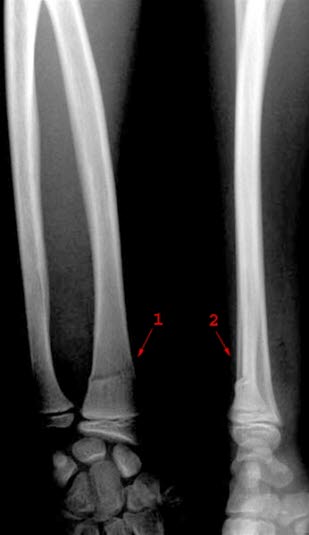

Fraktur (1 og 2) distalt i radius med lett bakovervinkling av distale fragment (1 og 2). Benet er bøyd, men ikke løsnet